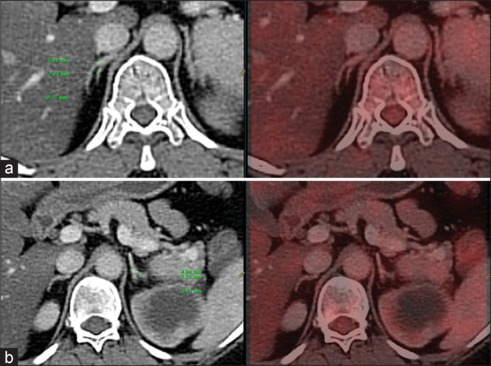

Detection of adrenal lesions either incidentally, or in symptomatic cases and/or during staging/restaging of oncological cases, it is very crucial to know the adrenal lesion is benign or malignant. Fluorodeoxyglucose positron emission tomography-computed tomography (FDG PET/CT) helps in this comprehensive evaluating process. Here, we present the most frequently facing adrenal lesions in routine oncological PET/CT scans. The aim of this presentation is to know the FDG uptake spectrum of various adrenal lesions on PET/CT scan so that increase the diagnostic accuracy and spectrum of differential diagnosis.

Abstract Image